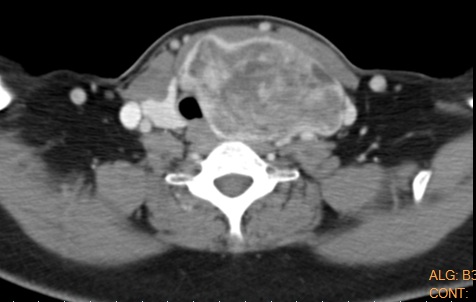

A thyroid goiter refers to an enlarged thyroid gland. The thyroid gland is a hormone gland, which is situated in the lower part of the neck. Similar to the shape of a butterfly or a bowtie, it has a left and a right side connected with a smaller central area. Generally, it should not be any larger than the size of the typical bowtie.

Occasionally, the thyroid may grow in size and give patients complications due to its size. This growth could be due to a single nodule within the thyroid, which could otherwise be suspicious for a growth. Alternatively, a multinodular goiter is more of a benign process that creates a large bulk of thyroid tissue within the neck. Certain families have more pre-disposition to thyroid goiters within their gene pools. Also, in some areas of the world, goiters are endemic where iodine is low in diet supplements.

A thyroid goiter may initially be more of a cosmetic concern due to large mass within the front of the neck. With the passage of time, the goiter may grow in size and subsequently give compressive symptoms to the windpipe (larynx and trachea) as well as the swallowing mechanisms (esophagus). These symptoms become more manifest when the patient is lying on their back and the large bulk of thyroid falls down with gravity, almost choking certain patients. Larger goiters can also intrinsically constrict the windpipe and give symptoms similar to asthma.